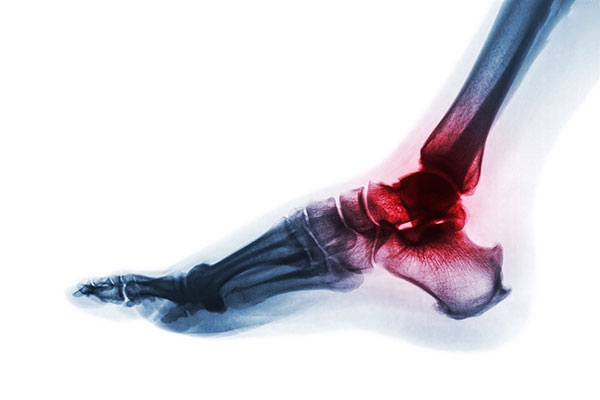

Đau gót chân: Nguyên nhân, triệu chứng, điều trị và phòng ngừa

Đau gót chân là tình trạng phổ biến do nhiều nguyên nhân như viêm cân gan chân, gai xương gót hoặc chấn thương mô mềm. Cơn đau có thể xuất hiện vào buổi sáng khi bước chân đầu tiên hoặc sau khi đứng lâu, gây khó chịu và ảnh hưởng đến khả năng di chuyển. Việc điều trị bao gồm nghỉ ngơi, sử dụng giày phù hợp, vật lý trị liệu hoặc trong một số trường hợp cần can thiệp y khoa.

Đau gót chân

Đau gót chân là gì?

Gót chân là bộ phận trồi lên ở cuối bàn chân, được cấu thành từ xương gót chân – cũng là xương lớn nhất trong bàn chân.

Đau gót chân là tình trạng đau gót chân trái hoặc đau gót chân phải, thường xảy ra khi  di chuyển nhiều, đứng quá lâu hoặc mang vác vật nặng gây ra,… Tuy nhiên, nguyên nhân gây đau gót chân không phải lúc nào cũng đơn giản như vậy, nó có thể liên quan đến một bệnh lý nào đó ở gót chân cần được thăm khám, điều trị sớm.